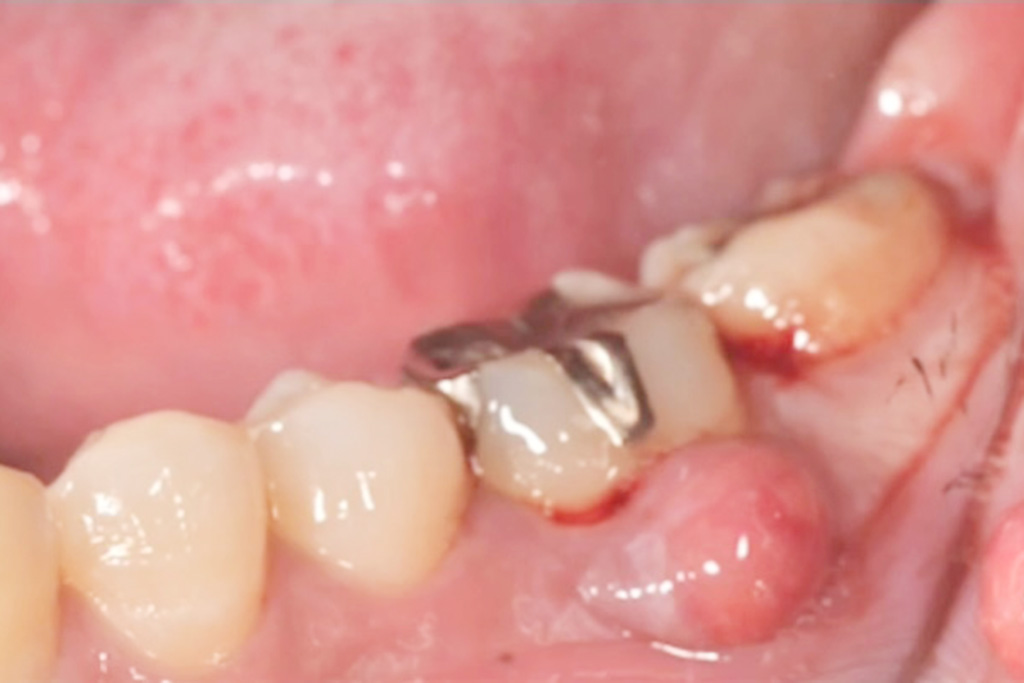

以前は、根尖病変などから

排膿している歯肉の開口部を

【フィステル(瘻孔)】と呼んでいました。

しかし現在は、

サイナストラクト(sinus tract)

という名称が使われることが増えています。

一方、歯科で見られる多くの排膿路は、

そのため、より正確な用語として

【サイナストラクト(排膿路)】が

用いられるようになりました。

臨床でも「フィステルですね」ではなく

「サイナストラクトが認められます」と

表現する流れになっています。